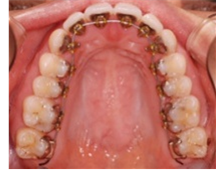

『矯正は子どもしかできない』と思い込んでいませんか?

大人の方は審美的な面での改善を目的として来られることが多いようです。

出っ歯や、受け口、八重歯など、外見を気にして治療を始められます。

しかし、ご自分の意志で、美しい口元を目標に歯列矯正治療に望む大人の歯列矯正治療は、歯みがきや装置の手入れなどにも気を配ることができ、口腔内が良い状態で、効率的に治療が進むことも多いのです。